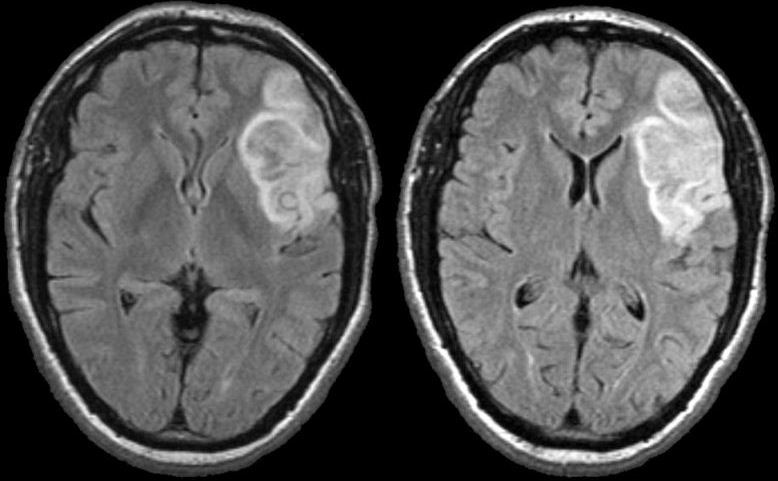

Stroke Syndrome:

In a right handed patient…

Right MCA Stem occlusion